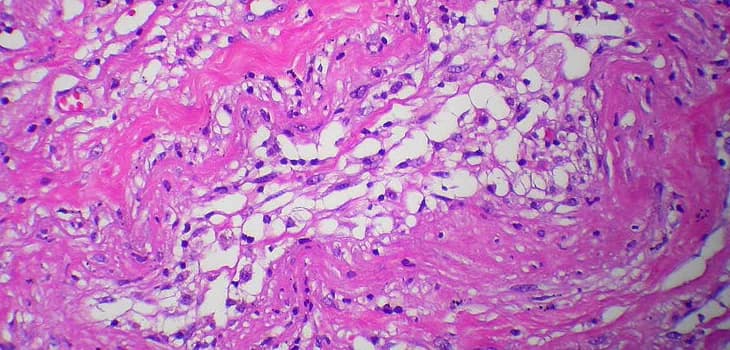

For several years, adipose tissue has been gaining increasing interest as an ideal source of mesenchymal stem cells for regenerative treatment of various...